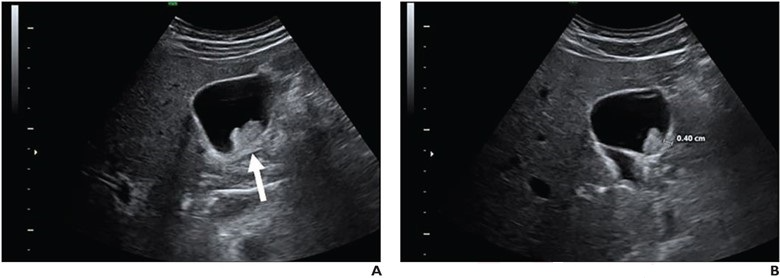

42-year-old man who presented with right upper quadrant pain. Transverse (A) and sagittal (B) greyscale ultrasound images of gallbladder show 25-mm nonmobile sessile polyp with adjacent wall thickening (arrow, A; calipers, B). Polyp was classified as extremely low risk by no readers, low risk by 4 readers, and indeterminate risk by 6 readers. Surgical consultation was recommended by all 10 readers. Pathologic assessment from cholecystectomy yielded adenoma, consistent with benign neoplastic polyp.